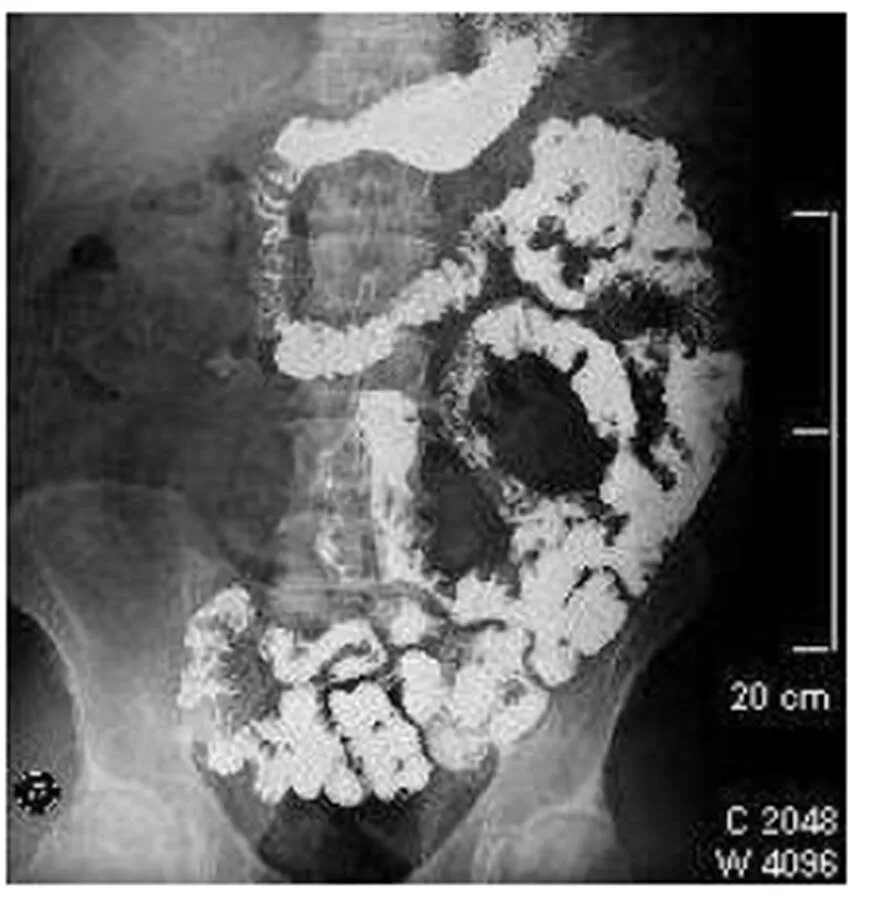

In upper endoscopy, a hemorrhagic duodenitis was found with active bleeding by a visible vessel that was stopped after combined endoscopic therapy (Fig. 2 and 3).

Figure 2: Upper endoscopic findings A visible vessel after endoscopic therapy located in the

duodenal bulb is observed

The blood cell count was normal, and celiac serological tests were negative. After a month, there was an endoscopic control with evidence of severe duodenitis, and biopsy revealed hyaline deposits in the walls of blood vessels and extravascular area positive for Congo red staining with birefringence under polarized light (Fig. 4 and 5).

Figure 3: Upper endoscopic findings The descending duodenum is edematous with recent

bleeding due to intestinal amyloidosis